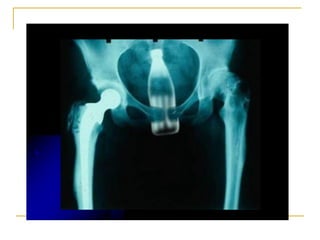

EFECTOS COLATERALES Y  TOXICOS  SNC:   Hiperexcitabilidad Ansiedad Temblor de cuerpo Convulsiones clónicas Parálisis respiratoria Depresión del SNC SCV Hipotensión Bradicardia Hipersensibilidad Prurito Asma bronquial Choque anafiláctico Los efectos tóxicos se producen en: Locales Ulceración mucosa Dolor en el sitio de la inyección Lesiones nerviosas Mordedura de labio Necrosis locales